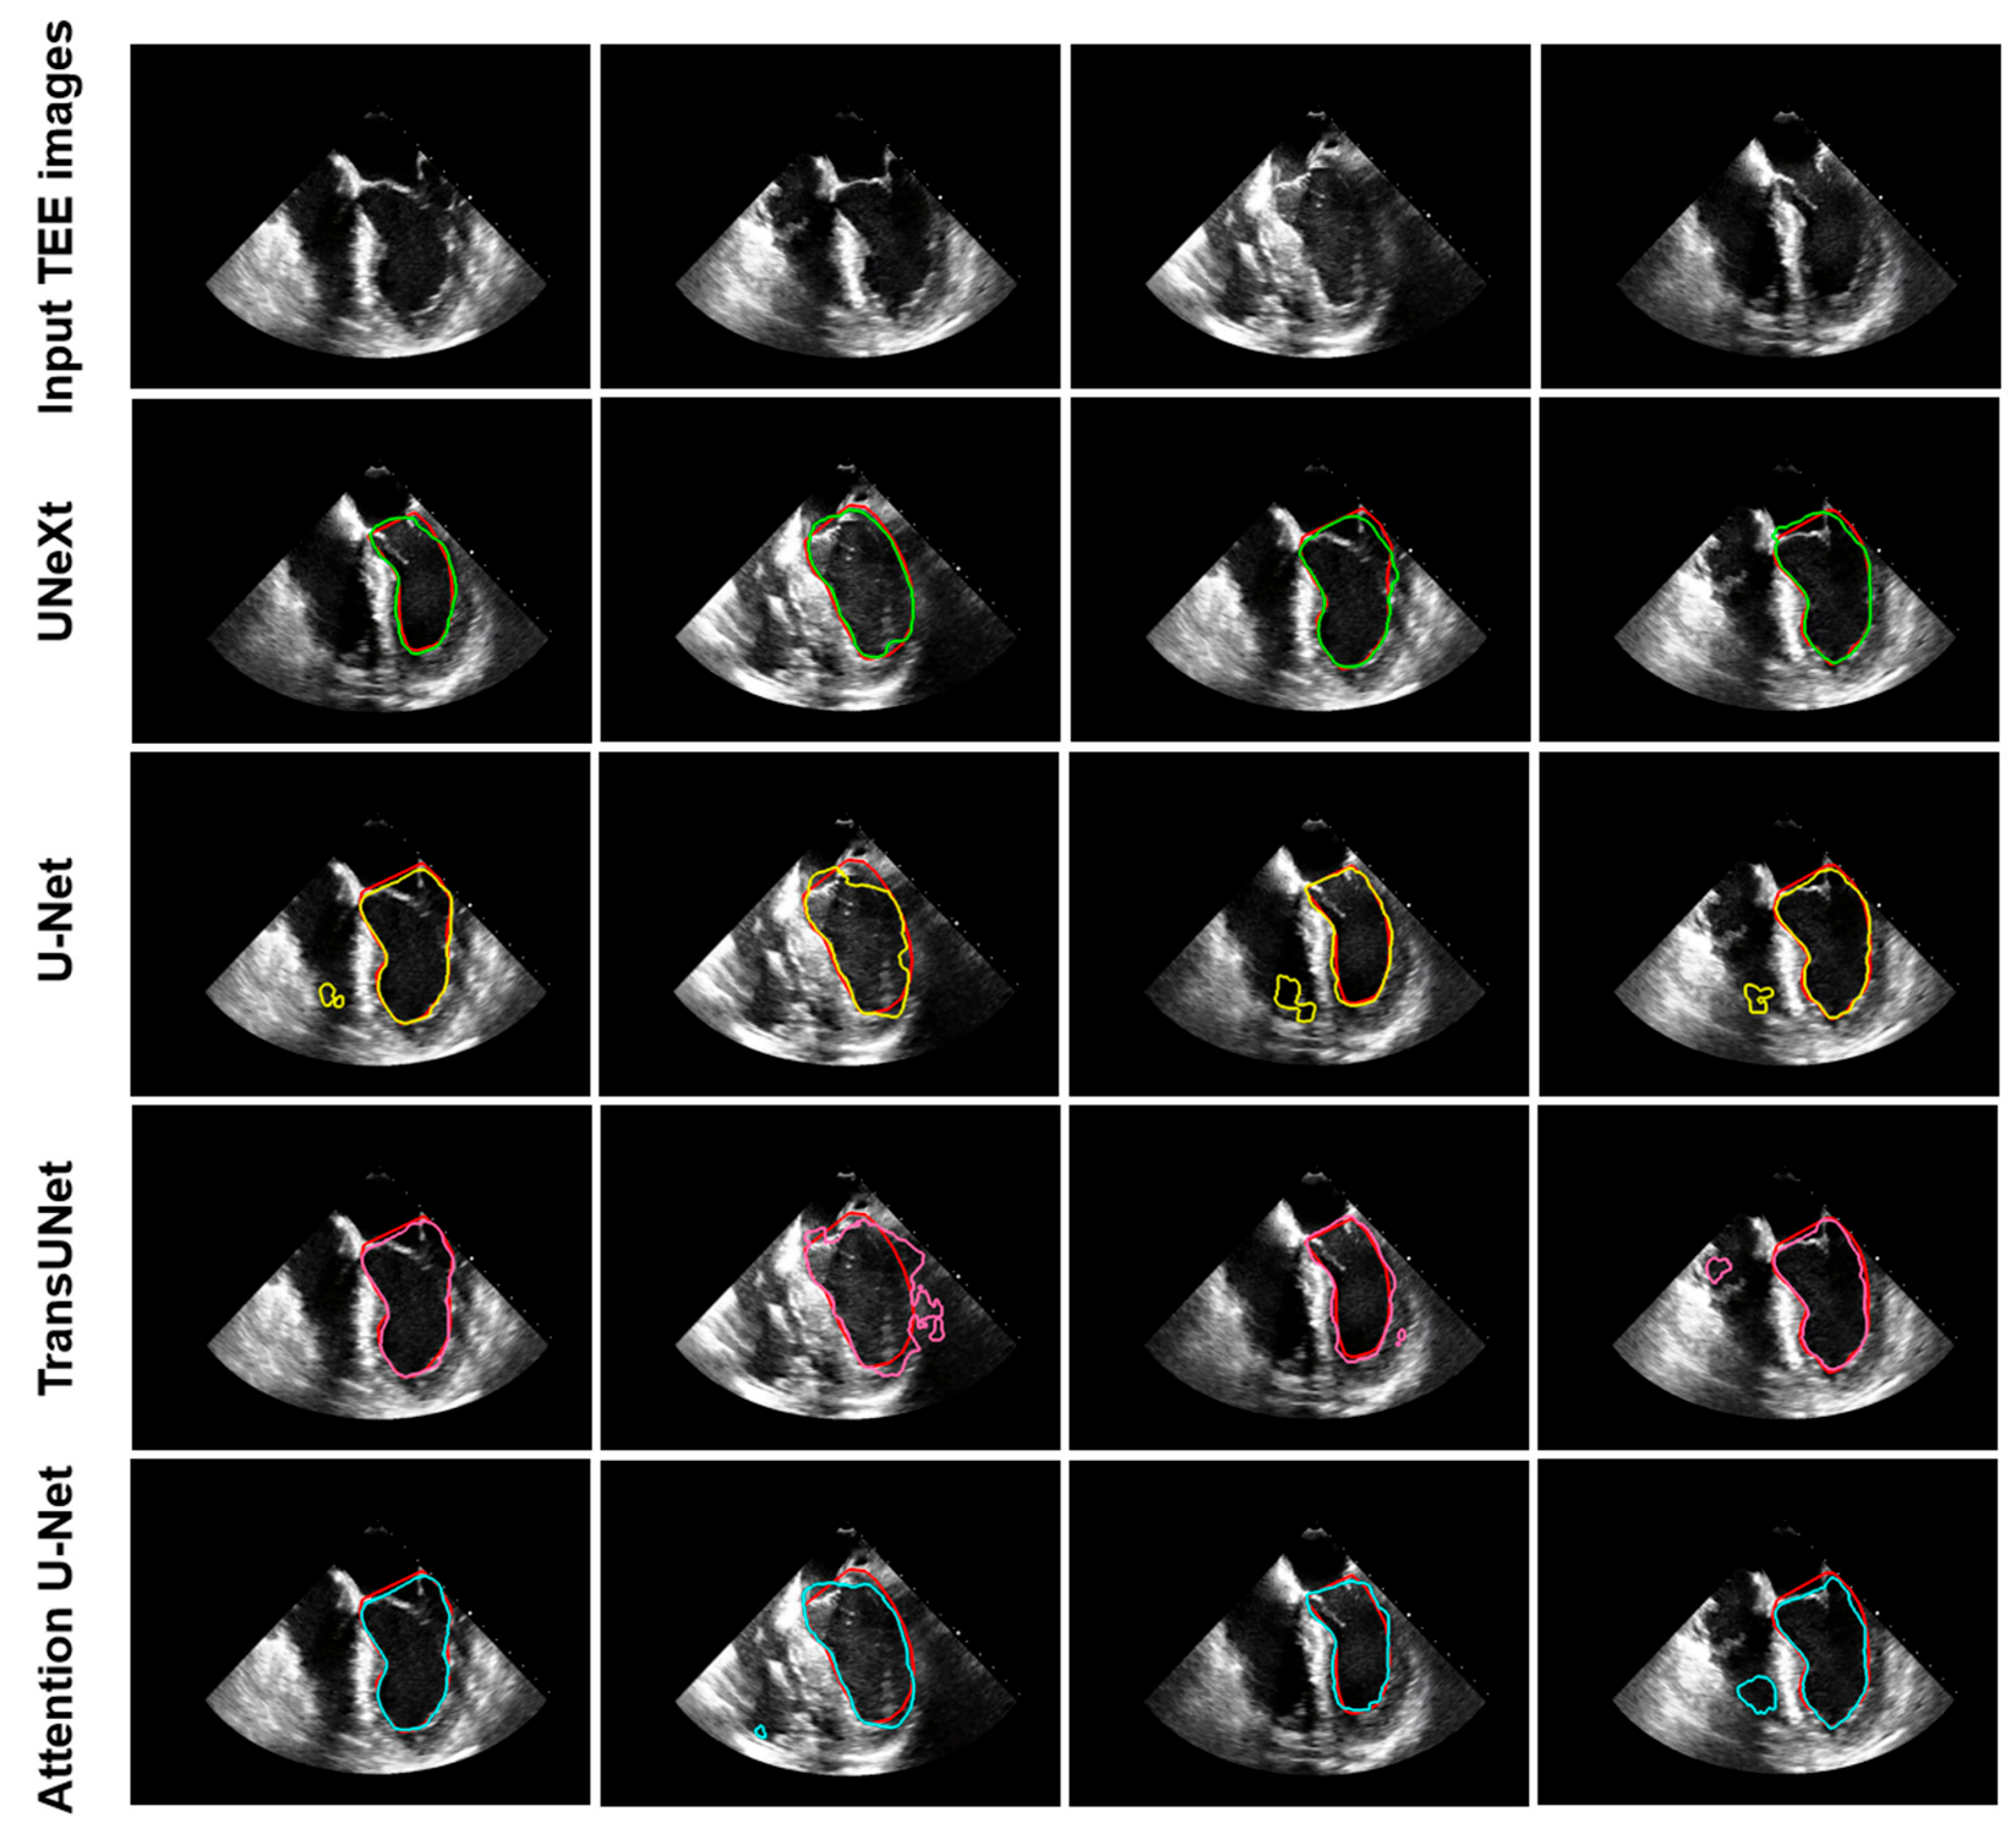

| Deep Learning Models | DSC (%) | IoU (%) |

|---|---|---|

| U-Net [5] TransUNet [12] | 87.76 ± 3.61 85.75 ± 5.93 | 76.61 ± 7.45 77.35 ± 8.50 |

| Attention U-Net [11] | 79.98 ± 9.26 | 68.86 ± 11.95 |

| UNeXt [26] | 88.60 ± 2.92 | 77.60 ± 6.33 |